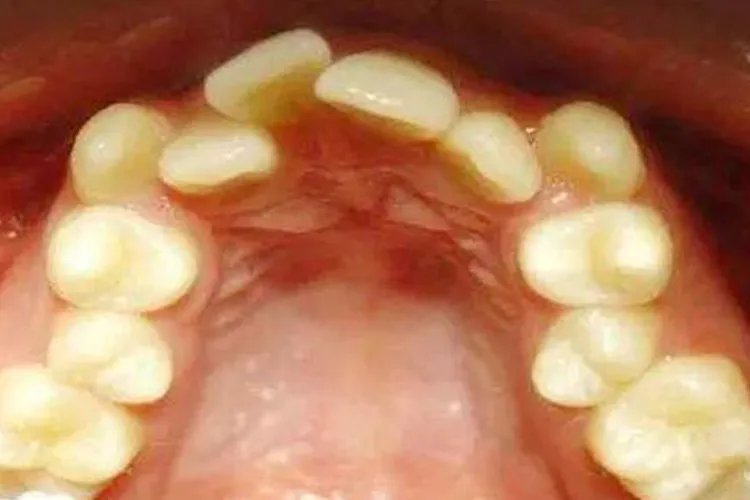

概述牙齿不整齐即牙列不齐,是错(牙合)畸形的典型表现之一,包括牙列拥挤、牙列间隙等。牙列不齐可能与遗传因素以及后天因素有关,比如疾病、口腔不良习惯等。症状牙列不齐常见类型包括牙列拥挤、牙列间隙等,具体症状有所不同。牙列拥挤表现为个别牙或多个牙在各个方向的错位,如唇(颊)舌向错位、近远中向错位、高位、低位、扭转等。牙列拥挤可能影响牙弓形态或上下颌牙弓关系,可表现为牙弓形态不规则或不对称,前牙覆(牙合)覆盖异常,后牙区拥挤并伴后牙反(牙合)、锁(牙合)。牙列间隙表现为牙和牙之间有间隙。根据牙列间隙的病因不同,伴有相应的临床表现,比如颌骨过大,牙齿数量少或形态小。